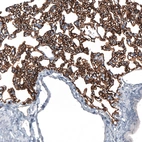

Immunohistochemistry analysis in human lung and prostate tissues using AMAb91635 antibody. Corresponding AGER RNA-seq data are presented for the same tissues.